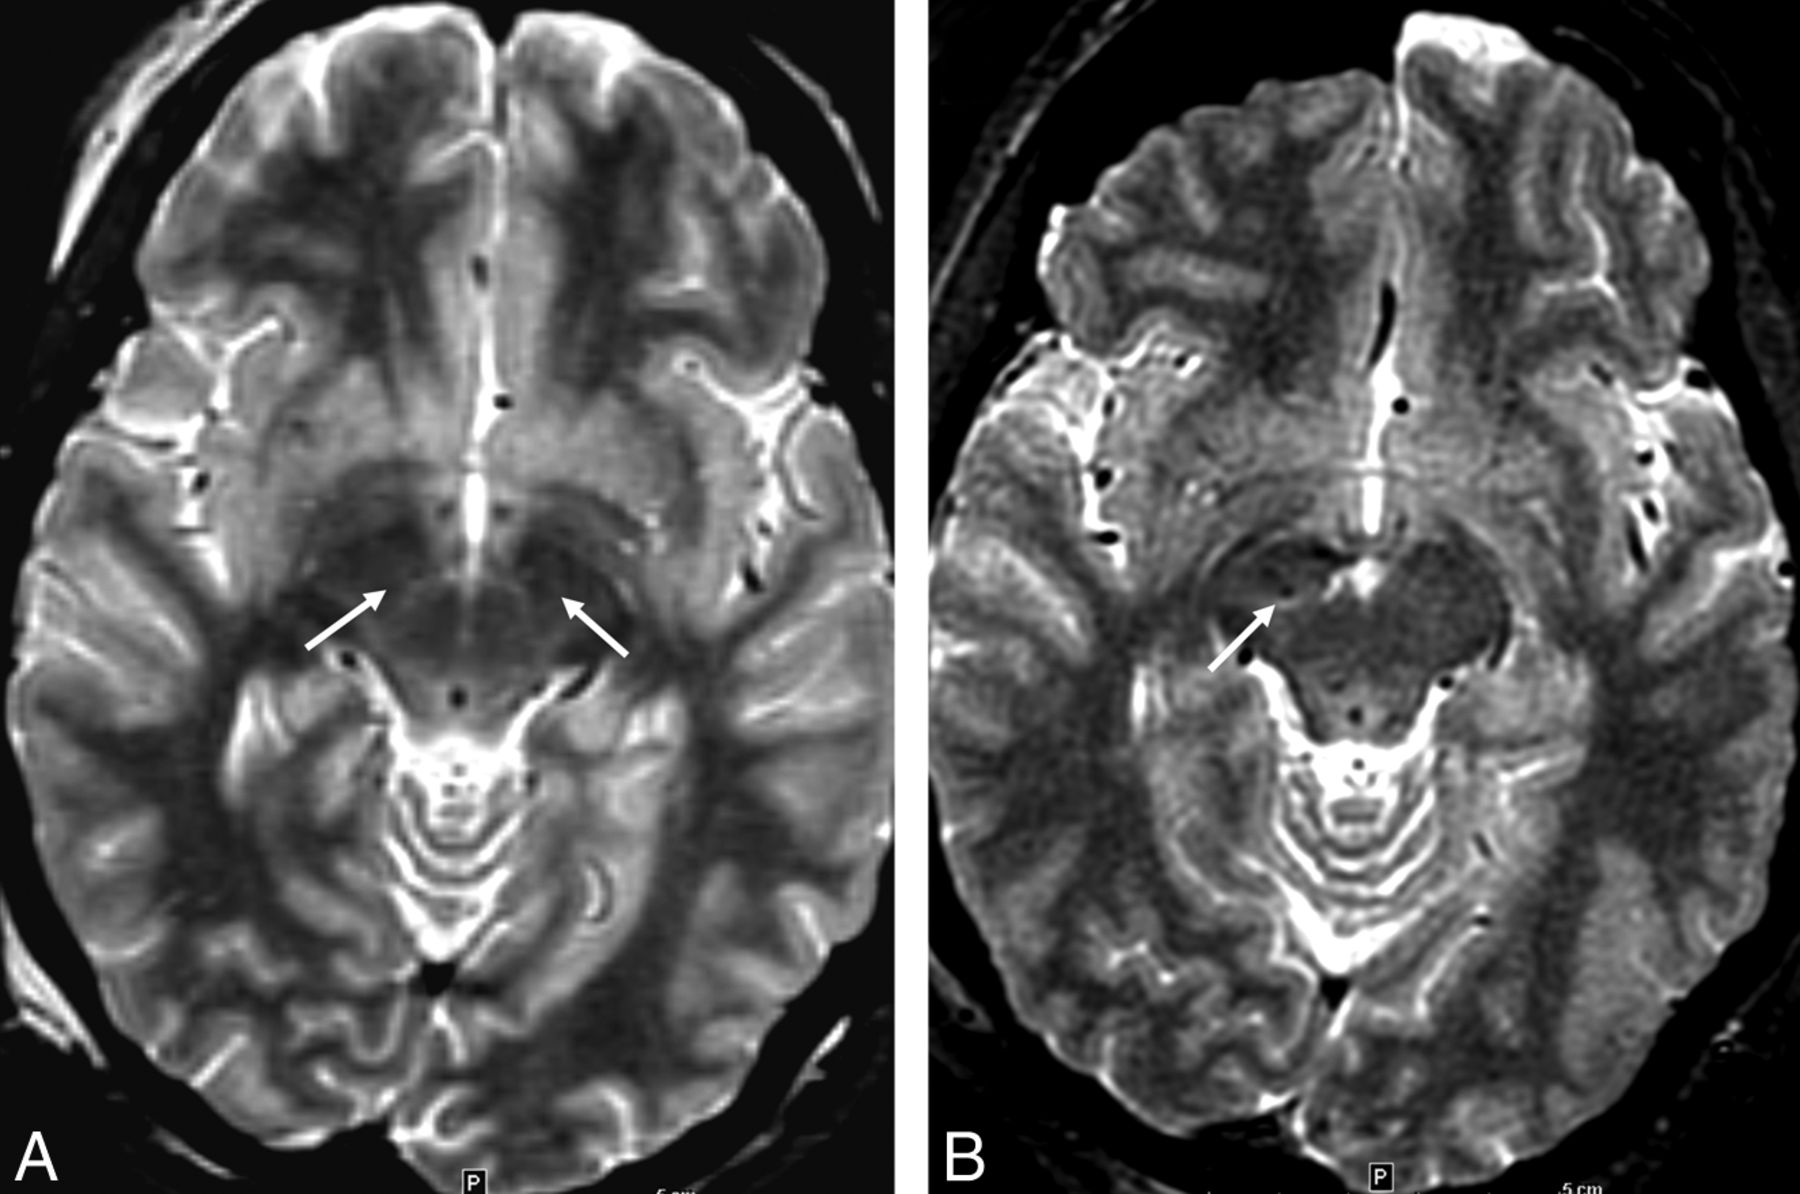

Example of lower STN conspicuity occasionally seen on low-SAR imaging, A, Presurgical image from high-SAR (1.5 W/kg) FSTIR MR imaging with adequate tissue contrast allowing MR imaging–based STN coordinate measurements (arrows). B, Subsequent postsurgical low-SAR FSTIR image (0.1 W/kg). Notice slightly lower STN contrast causing the coordinate estimation or assessment of the right lead position to be somewhat difficult (arrow) and requiring use of other landmarks and microelectrode recording.